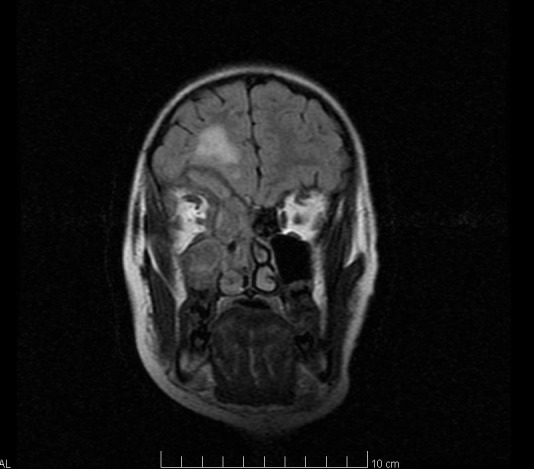

Imaging tests (brain CT and brain MRI) highlight right frontal lobe abscess (Fig. 2 – yellow arrow), medial orbital wall osteitis – right orbit (Fig. 1 – blue arrow, Fig. 2 – blue arrow), maxillary sinusitis, right ethmoidal and sphenoidal sinusitis (Fig. 1 – red arrow, Fig. 2 – red arrow).